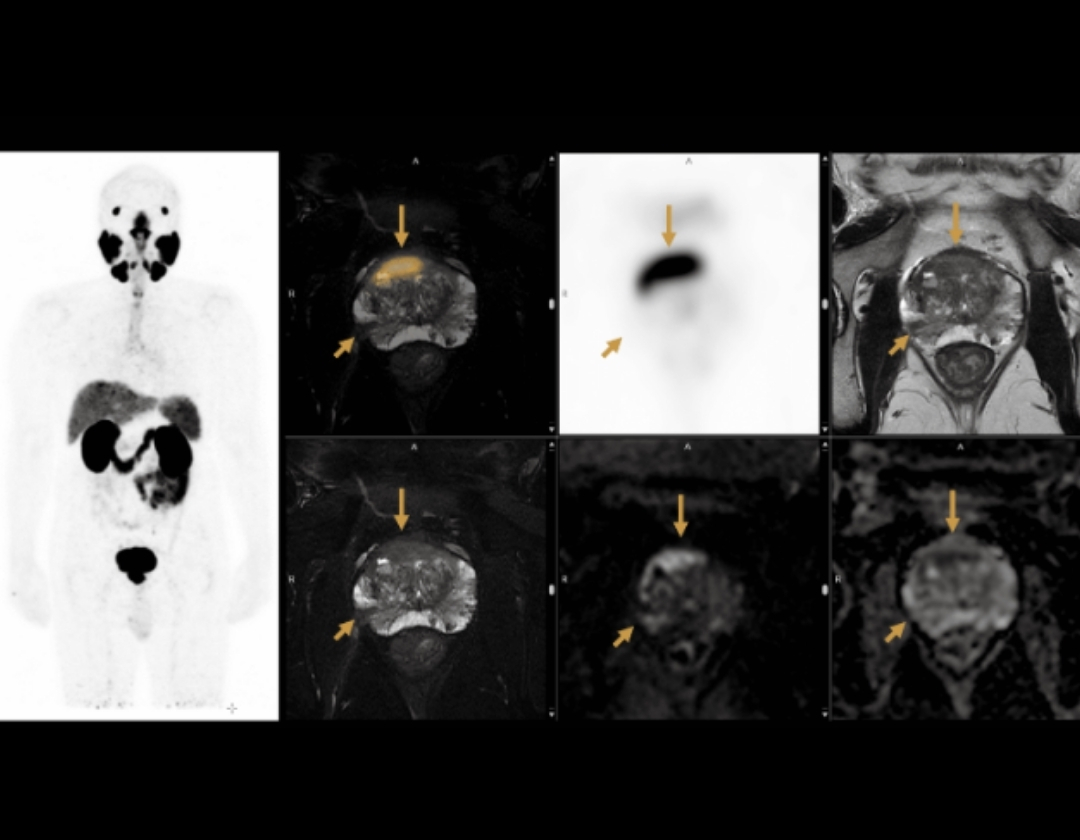

Assessment of prostate cancer